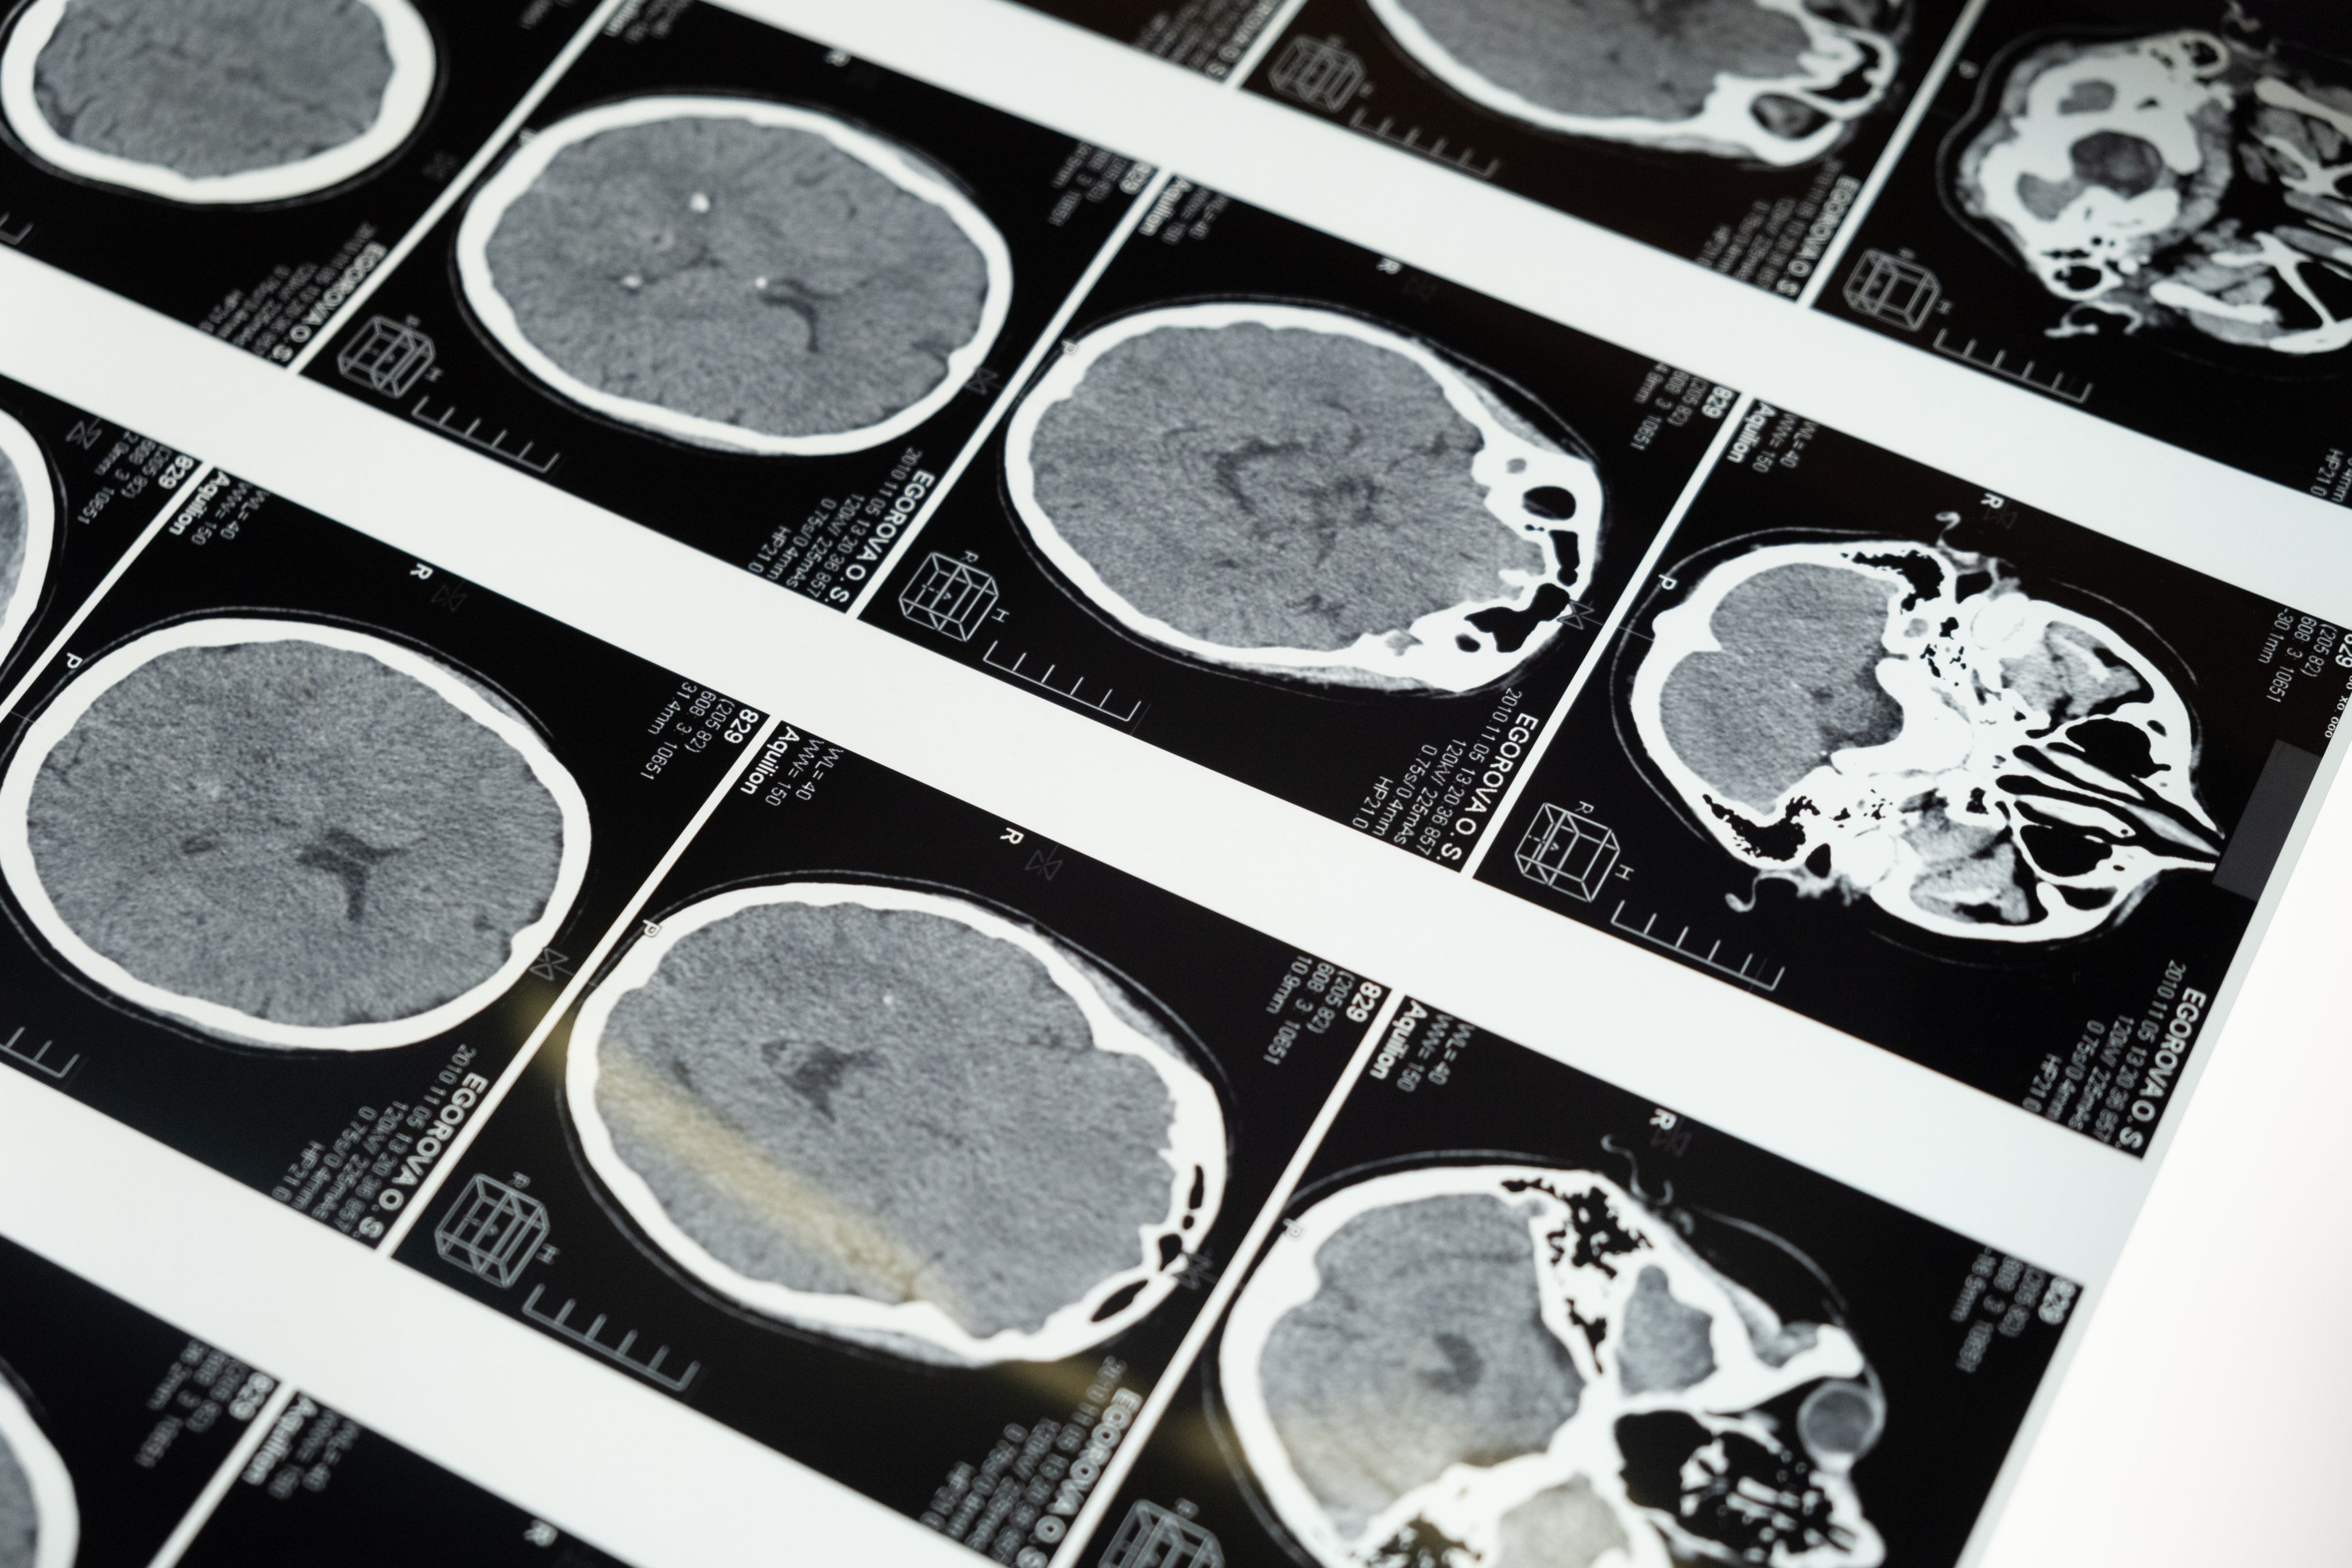

Take a look here:

Chart is done by Christian Gardecki. This chart is based on Data given from UNITE Brain Bank at Boston University